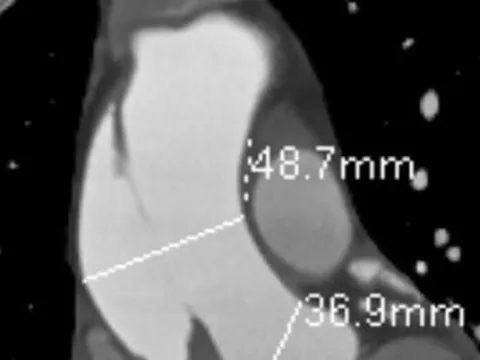

Đau ngực kéo dài, coi chừng đột tử

Nữ bệnh nhân nhập viện trong tình trạng bị đau ngực kéo dài không rõ nguyên nhân. Qua chẩn đoán hình ảnh, bác sĩ phát hiện bệnh nhân bị lóc thành động mạch, nguy cơ đột tử bất kỳ lúc nào.